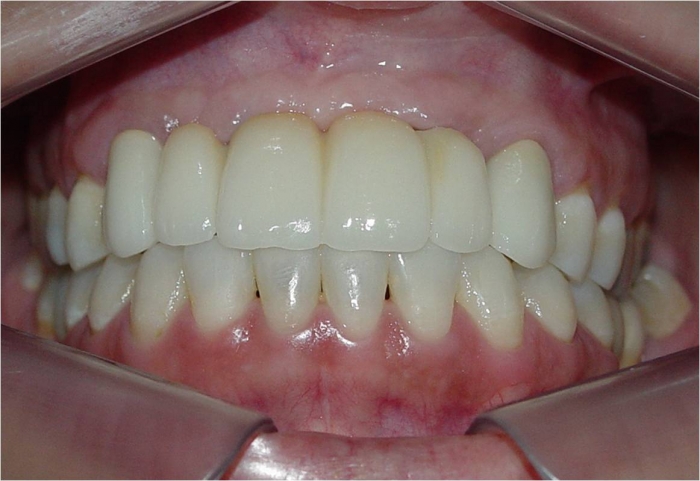

Imagem final

Próteses fixas em porcelana instaladas

Sorriso final, do caso terminado em Novembro de 2013